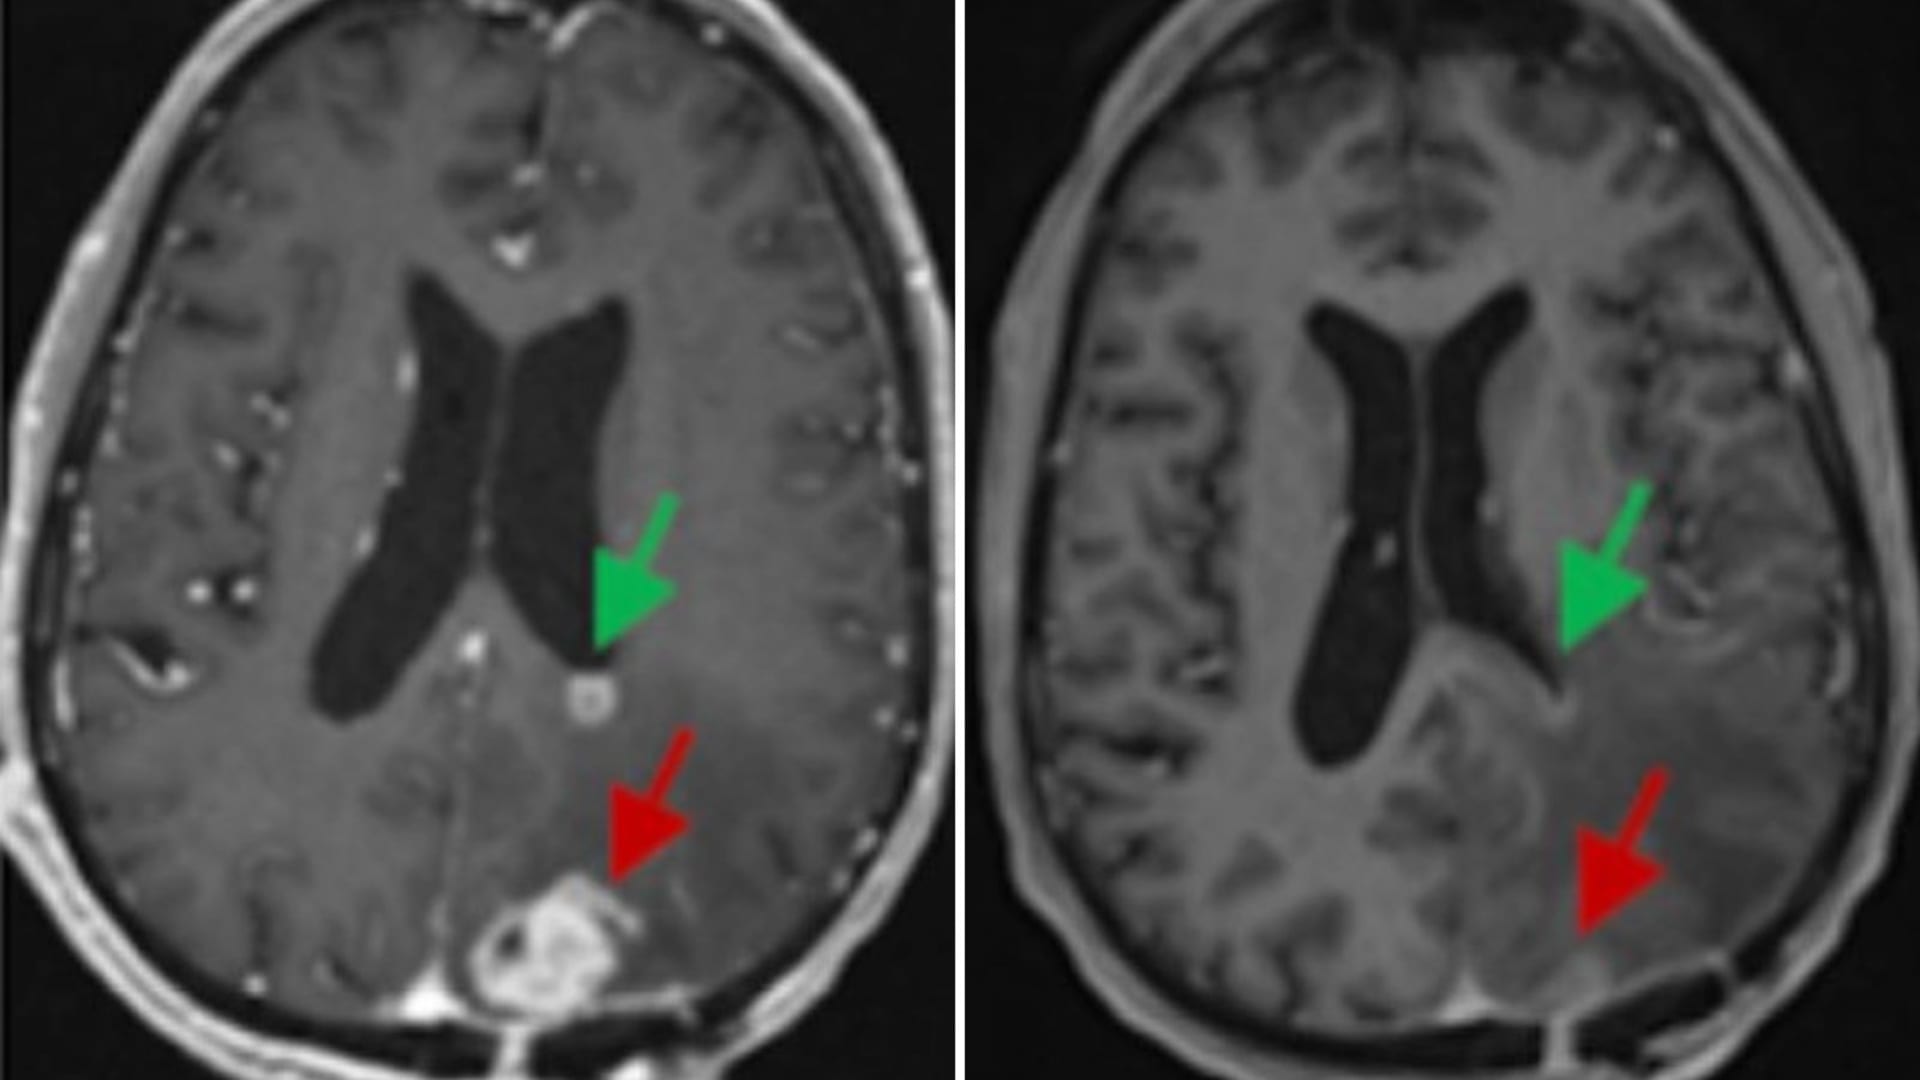

الأدوية الحية تُظهر نتائج واعدة ضد أورام المخ التي يصعب علاجها

الأدوية الحية تُظهر نتائج واعدة ضد أورام المخ التي يصعب علاجها 6